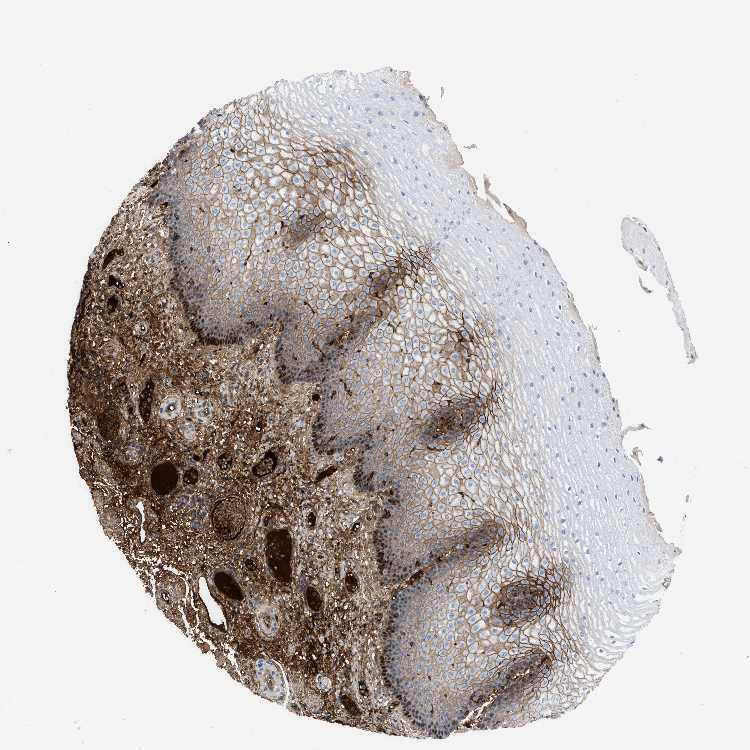

ESOPHAGUS - Antibody stainingi

Antibody staining in the annotated cell types in the current human tissue is reported as not detected, low, medium, or high, based on conventional immunohistochemistry profiling in selected tissues. This score is based on the combination of the staining intensity and fraction of stained cells.

Each image is clickable and will lead to virtual microscopy that enables deeper exploration of all samples and also displays staining intensity scores, fraction scores and subcellular localization as well as patient and tissue information for each sample.

Antibody HPA002087Antibody CAB019405

Squamous epithelial cells Not detectedHigh